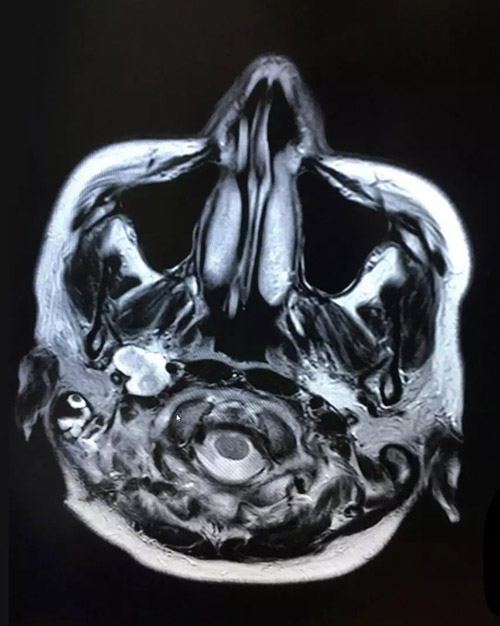

術(shù)后影像:右側(cè)橋小腦角區(qū),頸深部占位術(shù)后改變